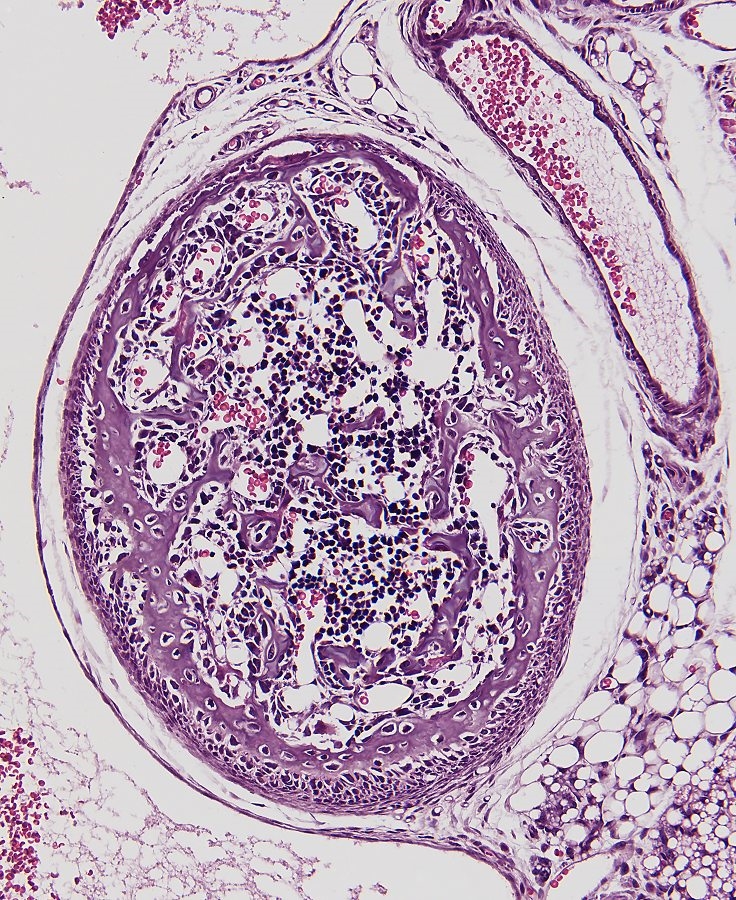

Wirbel mit Blutzellbildung, stitch von 6 Bilder, Objektiv Leitz Plan Fluotar 25x.

Sagittaler Schnitt von ein fünf tagen alte Maus. Schnittdicke 4µm.

Knochen werden Rosa angefärbt. Färbung: Klassische Hämatoxylin nach Gill und Eosin.